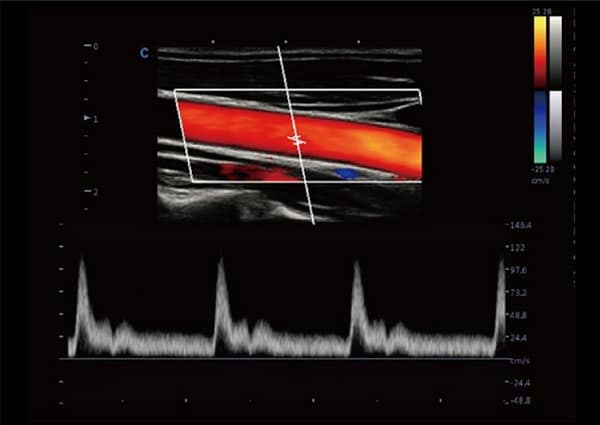

- Doppler Thông Minh: Tự động điều chỉnh hướng ROI và PFR, đem lại hiệu quả và dễ dàng đo lường hơn, tập trung vào bệnh nhân một cách tối ưu.

- SonoColor và SonoContrast: Cung cấp phân tích dòng định lượng và độ nhạy cao hơn, thích ứng với mọi loại đầu dò.